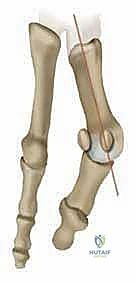

الفهم التشريحي العميق: ماذا يحدث داخل القدم عند الإصابة بالورم الأروح؟

لفهم عبقرية الجراحة التي يجريها الأستاذ الدكتور محمد هطيف، يجب أولاً أن نفهم ميكانيكية القدم. تتكون القدم البشرية من شبكة معقدة من العظام، الأربطة، والأوتار التي تعمل معاً لتوزيع وزن الجسم وتسهيل الحركة.

ورم إبهام القدم الأروح ليس مجرد "نمو عظمي زائد" كما يعتقد الكثيرون، بل هو خلل ميكانيكي وتشريحي معقد يصيب المفصل المشطي السلامي الأول (First Metatarsophalangeal Joint - MTP).

الآلية المرضية للتشوه:

* انحراف العظمة المشطية الأولى: تبدأ العظمة المشطية الأولى (العظمة الطويلة التي تسبق الإبهام) بالانحراف نحو الداخل (باتجاه القدم الأخرى).

* انحراف السلامية (الإبهام): كرد فعل، ينحرف إصبع الإبهام نفسه نحو الخارج (باتجاه الأصابع الصغيرة للقدم).

* بروز المفصل: هذا الانحراف المتعاكس يؤدي إلى بروز رأس العظمة المشطية الأولى، مكوناً الكتلة العظمية المؤلمة التي نراها من الخارج.

* الزاوية المفصلية المشطية البعيدة (DMAA): في الحالات المتقدمة، يتشوه سطح المفصل نفسه ويميل بزاوية غير طبيعية. الجراحات التقليدية تفشل في علاج هذه الزاوية، وهنا تبرز أهمية تقنية شفرون ثنائية المستوى التي يطبقها الدكتور هطيف لتصحيح هذه الزاوية بدقة متناهية.